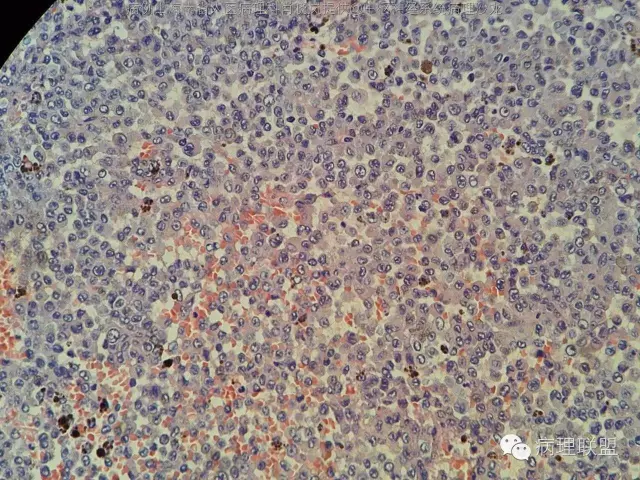

男,36岁。右面部麻木1月余。手术所见:右CPA区见5Ⅹ4cm肿块,灰褐色,血供丰富,质韧,界清。临床诊断:右侧桥小脑角区占位:脑膜瘤。大体检查:灰黑色碎组织一堆,大小2.5Ⅹ2.5x0.5cm,免疫S100,HMB45阳性。Ki67指数低。(病例由海南省人医病理科肖晓岚提供,致谢!)

这张图像和后三张怎么不一样差别辣么大,前几张弥漫的组织细胞样细胞,后几张呈巢的

前4张是一个视野,后4张是另一个视野。是同一个人。@周泉

因为S100,HMB45均阳性,形态也不象色素性神经鞘膜瘤,还是要考虑黑色素的肿瘤吧。S100广泛的阳性,EMA,pR不阳,不支持脑膜瘤吧@福建医大附一病理.王行富

@海南省人医病理科肖晓岚 嗯,黑色素细胞肿瘤,核分裂计数?

罕见吧,一张片都数完了,也没见一个确定的核分裂@福建医大附一病理.王行富

不过,有不少的炎症细胞,中粒比较多

@海南省人医病理科肖晓岚 那就黑色素细胞瘤